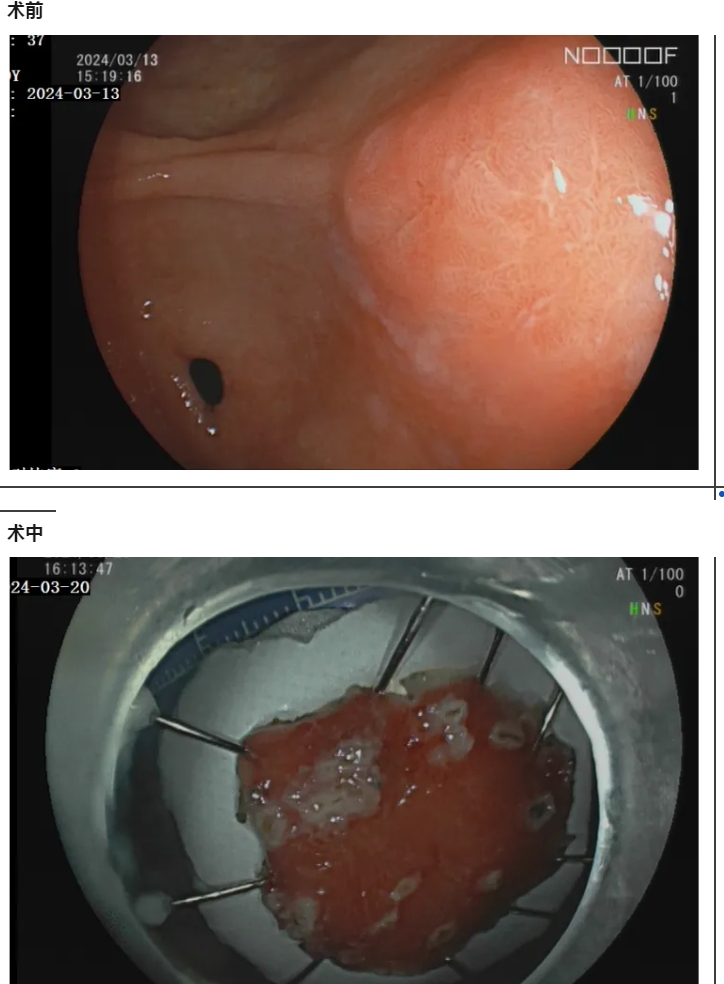

当前位置 :网站首页 > 党建长廊很多人出现症状后才会去医院看病,但消化道肿瘤早期很少有症状,等到出现症状时往往已是中晚期。近日,70岁的熊阿姨在做胃镜时意外查出胃早癌,由于发现及时,消化内科医生在内镜下为老人微创切除了病变,老人术后无需化疗,定期观察随访即可。专家提醒,七成以上早期胃癌无明显症状,高危人群要定期筛查。

熊阿姨今年70岁,一直胃就不好。近两年,她还出现间断恶心、剑突下隐痛,伴有食欲不振,夜间卧床睡觉时症状更重,整晚都睡不好觉,于是来到景德镇市第一人民医院消化内科就诊。通过胃镜检查,医生发现老人患有慢性非萎缩性胃炎伴胃窦糜烂,通过病理检查提示为高级别上皮内瘤变,医生诊断其为早期胃癌。

考虑到老人年事已高,身体状况较差,家属都很担心手术的风险。消化内科与心血管内科、麻醉科等多学科联合会诊后,制定了最佳的治疗方案,决定为熊阿姨行内镜黏膜下剥离术(ESD)。消化内科主治医师杨康华介绍,“ESD术是通过胃镜完成操作的,避免了传统胃癌手术切除,可完整地切除病变,对患者来说创伤小、术后恢复快,手术风险相对降低。” 听到医生的手术方案后,患者家属心中的焦虑减轻了不少。

经过充分的术前准备,消化内科主任盛锦义为患者实施了内镜黏膜下剥离术,通过内镜操作,小心翼翼地完整剥离病灶。术后熊阿姨恢复得很好。

内镜黏膜下剥离术ESD(endoscopic submucosal dissecfion)属于内镜微创手术,随着内镜技术的不断完善和消化内镜的普及,越来越多的早期胃癌、肠癌、癌前病变及胃肠粘膜下疾病均可以在内镜下予以切除。相较于传统的开放性手术,ESD手术具备不改变消化道解剖结构、不开刀、体表无创口、创伤小、出血少、恢复快等优势,从而得到广大医生及患者的一致推崇。